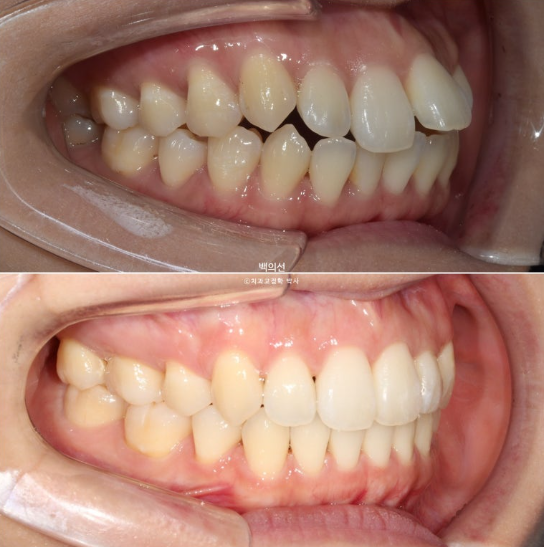

23.01~25.07

이제 전 후 비교해보겠습니다.